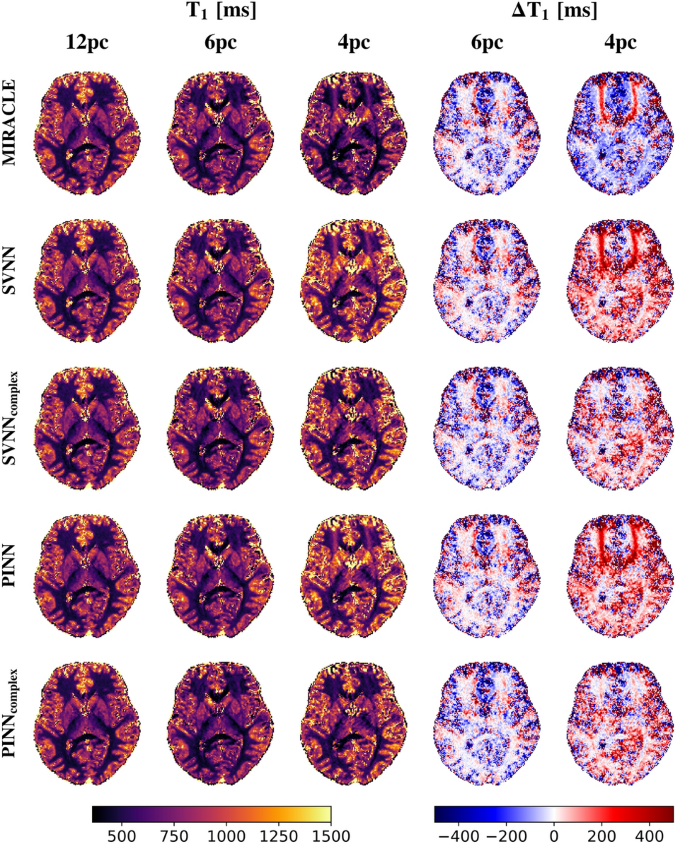

Consistent with the in silico results presented in Fig. 5, the trained complex-based DNNs demonstrate enhanced robustness to off-resonances for in vivo \(T_1\) (cf. Fig. 6) and \(T_2\) (cf. Fig. 7) relaxometry, in particular for a low number of phase cycles. At 12 phase cycles, the \(T_1\) and \(T_2\) maps of all investigated relaxometry frameworks appear very similar, while considerable differences arise in case the number of phase cycles is reduced to 4. In that case, both MIRACLE and standard magnitude-based DNNs show distinct regional patterns of pronounced under- and overestimations in \(T_1\) and \(T_2\) due to off-resonance sensitivity, in particular in frontal brain regions close to the sinuses reflecting the underlying inhomogeneities in \(B_0\) in those regions. Furthermore, MIRACLE tends to systematically underestimate \(T_1\) (cf. Fig. 6) and overestimate \(T_2\) (cf. Fig. 7) globally in brain tissue for \(N_{pc}=4\). The magnitude-based DNNs exhibit a tendency to systematically overestimate \(T_1\) for \(N_{pc}=4\), while no general systematic bias in the \(T_2\) estimates can be observed, but off-resonance-related artifacts persist. The complex-based DNNs achieve further improvement and effectively eliminate off-resonance-related artifacts and related systematic biases, especially at 4 phase cycles. Also in case of 6 phase cycles, the complex-based DNNs appear still superior to MIRACLE and magnitude-based DNNs with reduced absolute differences relative to the 12 phase cycle reference, e.g. in global WM.

Performance of complex-based DNN versus MIRACLE and magnitude-based DNN in vivo \(T_1\) estimation in case of accelerated pc-bSSFP acquisitions with only 6 and 4 phase cycles in comparison to the standard protocol with 12 phase cycles. A representative axial slice of the in vivo whole-brain \(T_1\) predictions of an unseen test subject obtained with 12, 6, and 4 phase cycles is shown in the first, second, and third column for each framework (MIRACLE, SVNN, \(SVNN_{complex}\), PINN, \(PINN_{complex}\), from top to bottom), respectively. The absolute differences \(\Delta T_1 = \hat{T}_1 - \hat{T}_{1, 12 pc}\) between the parameter predictions with 6 and 4 phase cycles relative to the reference with 12 phase cycles are shown in the fourth and fifth column, respectively.